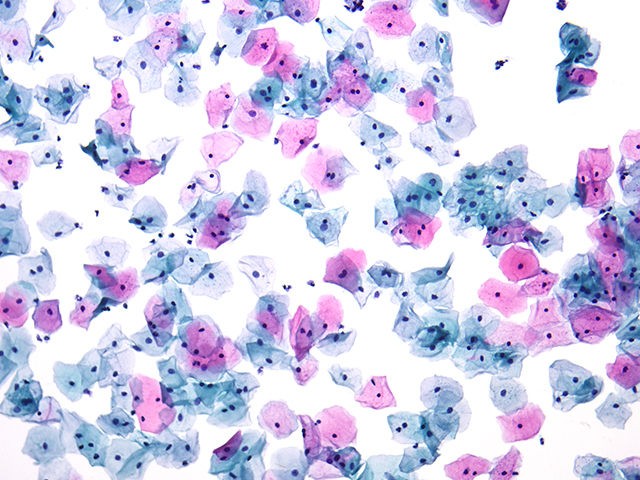

近期,有客戶針對組織切片拍照觀察提出了特定需求。其主要應用集中在病理和毒理生物組織切片的觀察拍照,因而急需一臺帶成像功能的生物顯微鏡。這要求顯微鏡能夠清晰地呈現組織切片的微觀結構,準確捕捉每一個關鍵細節(jié),以便為后續(xù)的分析診斷提供可靠依據。

明美提出了生物顯微鏡ML31 搭配高像素攝像頭解決方案。生物顯微鏡ML31 具備良好的光學性能,能夠提供清晰、穩(wěn)定的成像基礎。而與之搭配的大靶面高像素相機更是如虎添翼,在明場拍照時可以呈現出清晰的圖像效果。